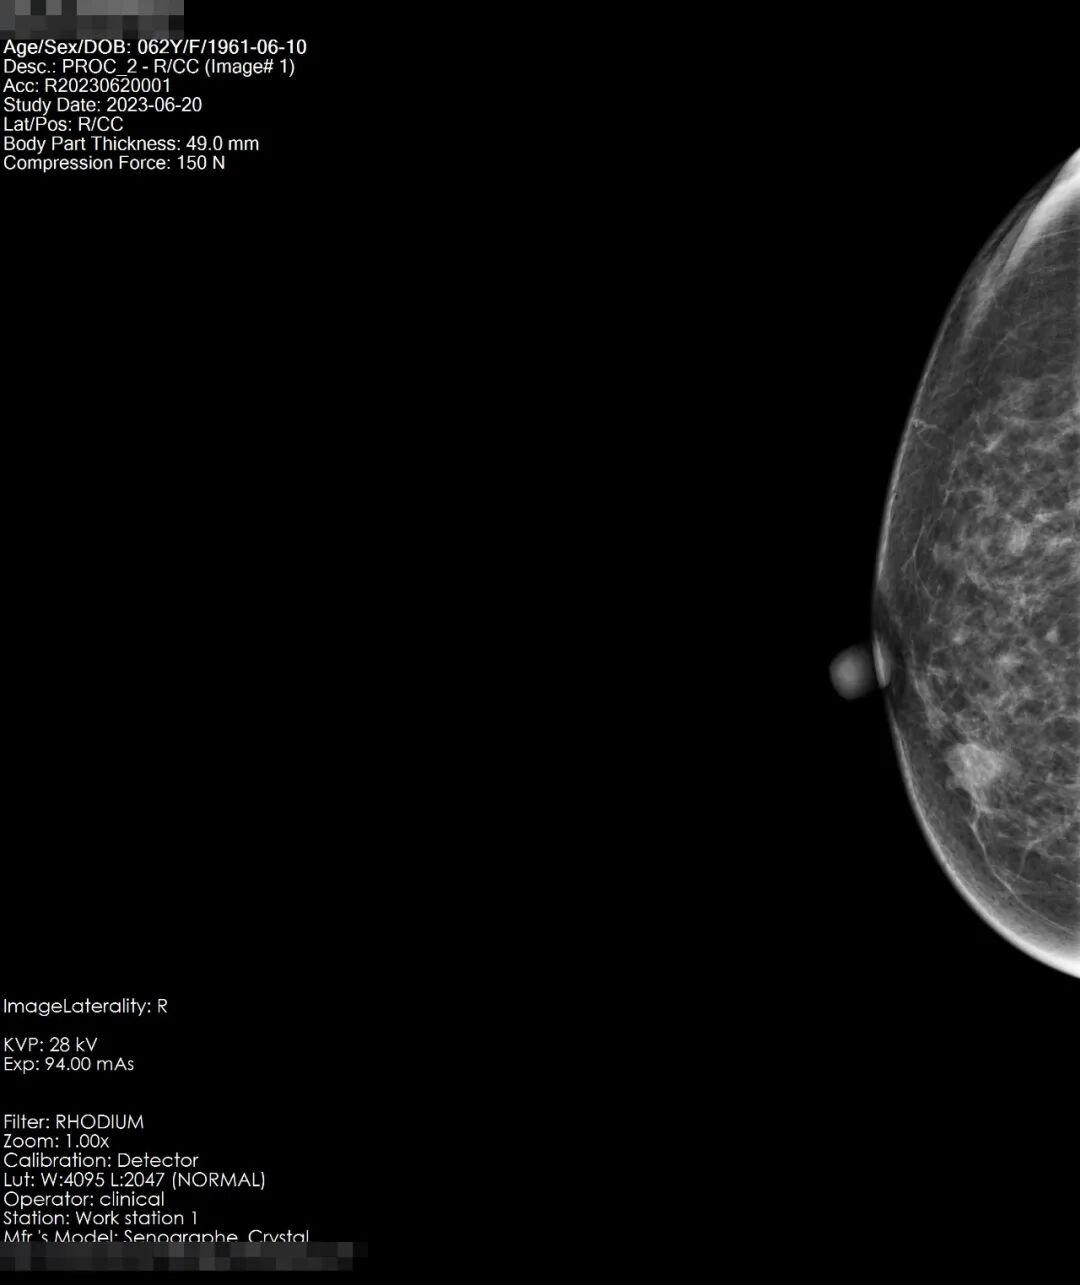

患者吴女士,58岁,在偶然一次洗澡发现自己右乳的乳头发硬并有变大的趋势,于是在网上找到了“自检”的小科普,对着镜子,开始自检,触及有疼痛感,遂即至宏宇浣江医院放射科,行乳腺钼靶检查。

检查所见:双乳腺呈散在纤维腺体型,乳腺组织丰富呈斑片状密度影,右乳内下像限见一密度增高结节影,大小约14*11mm左右,略呈分叶状,边界尚清,未见毛刺及成簇细小钙化。左乳未见明显异常,双侧腋下小淋巴结显示。双乳皮肤光整,皮下组织结构清晰,双乳头无殊。

结果显示:右乳内下像限结节,建议穿刺活检,(BI-RADS-Ⅳb类)。双侧腋下小淋巴结显示。

患者于8月2日至杭州邵逸夫医院进行全麻手术,术后病理结果为乳腺浸润性癌I期<早期>。